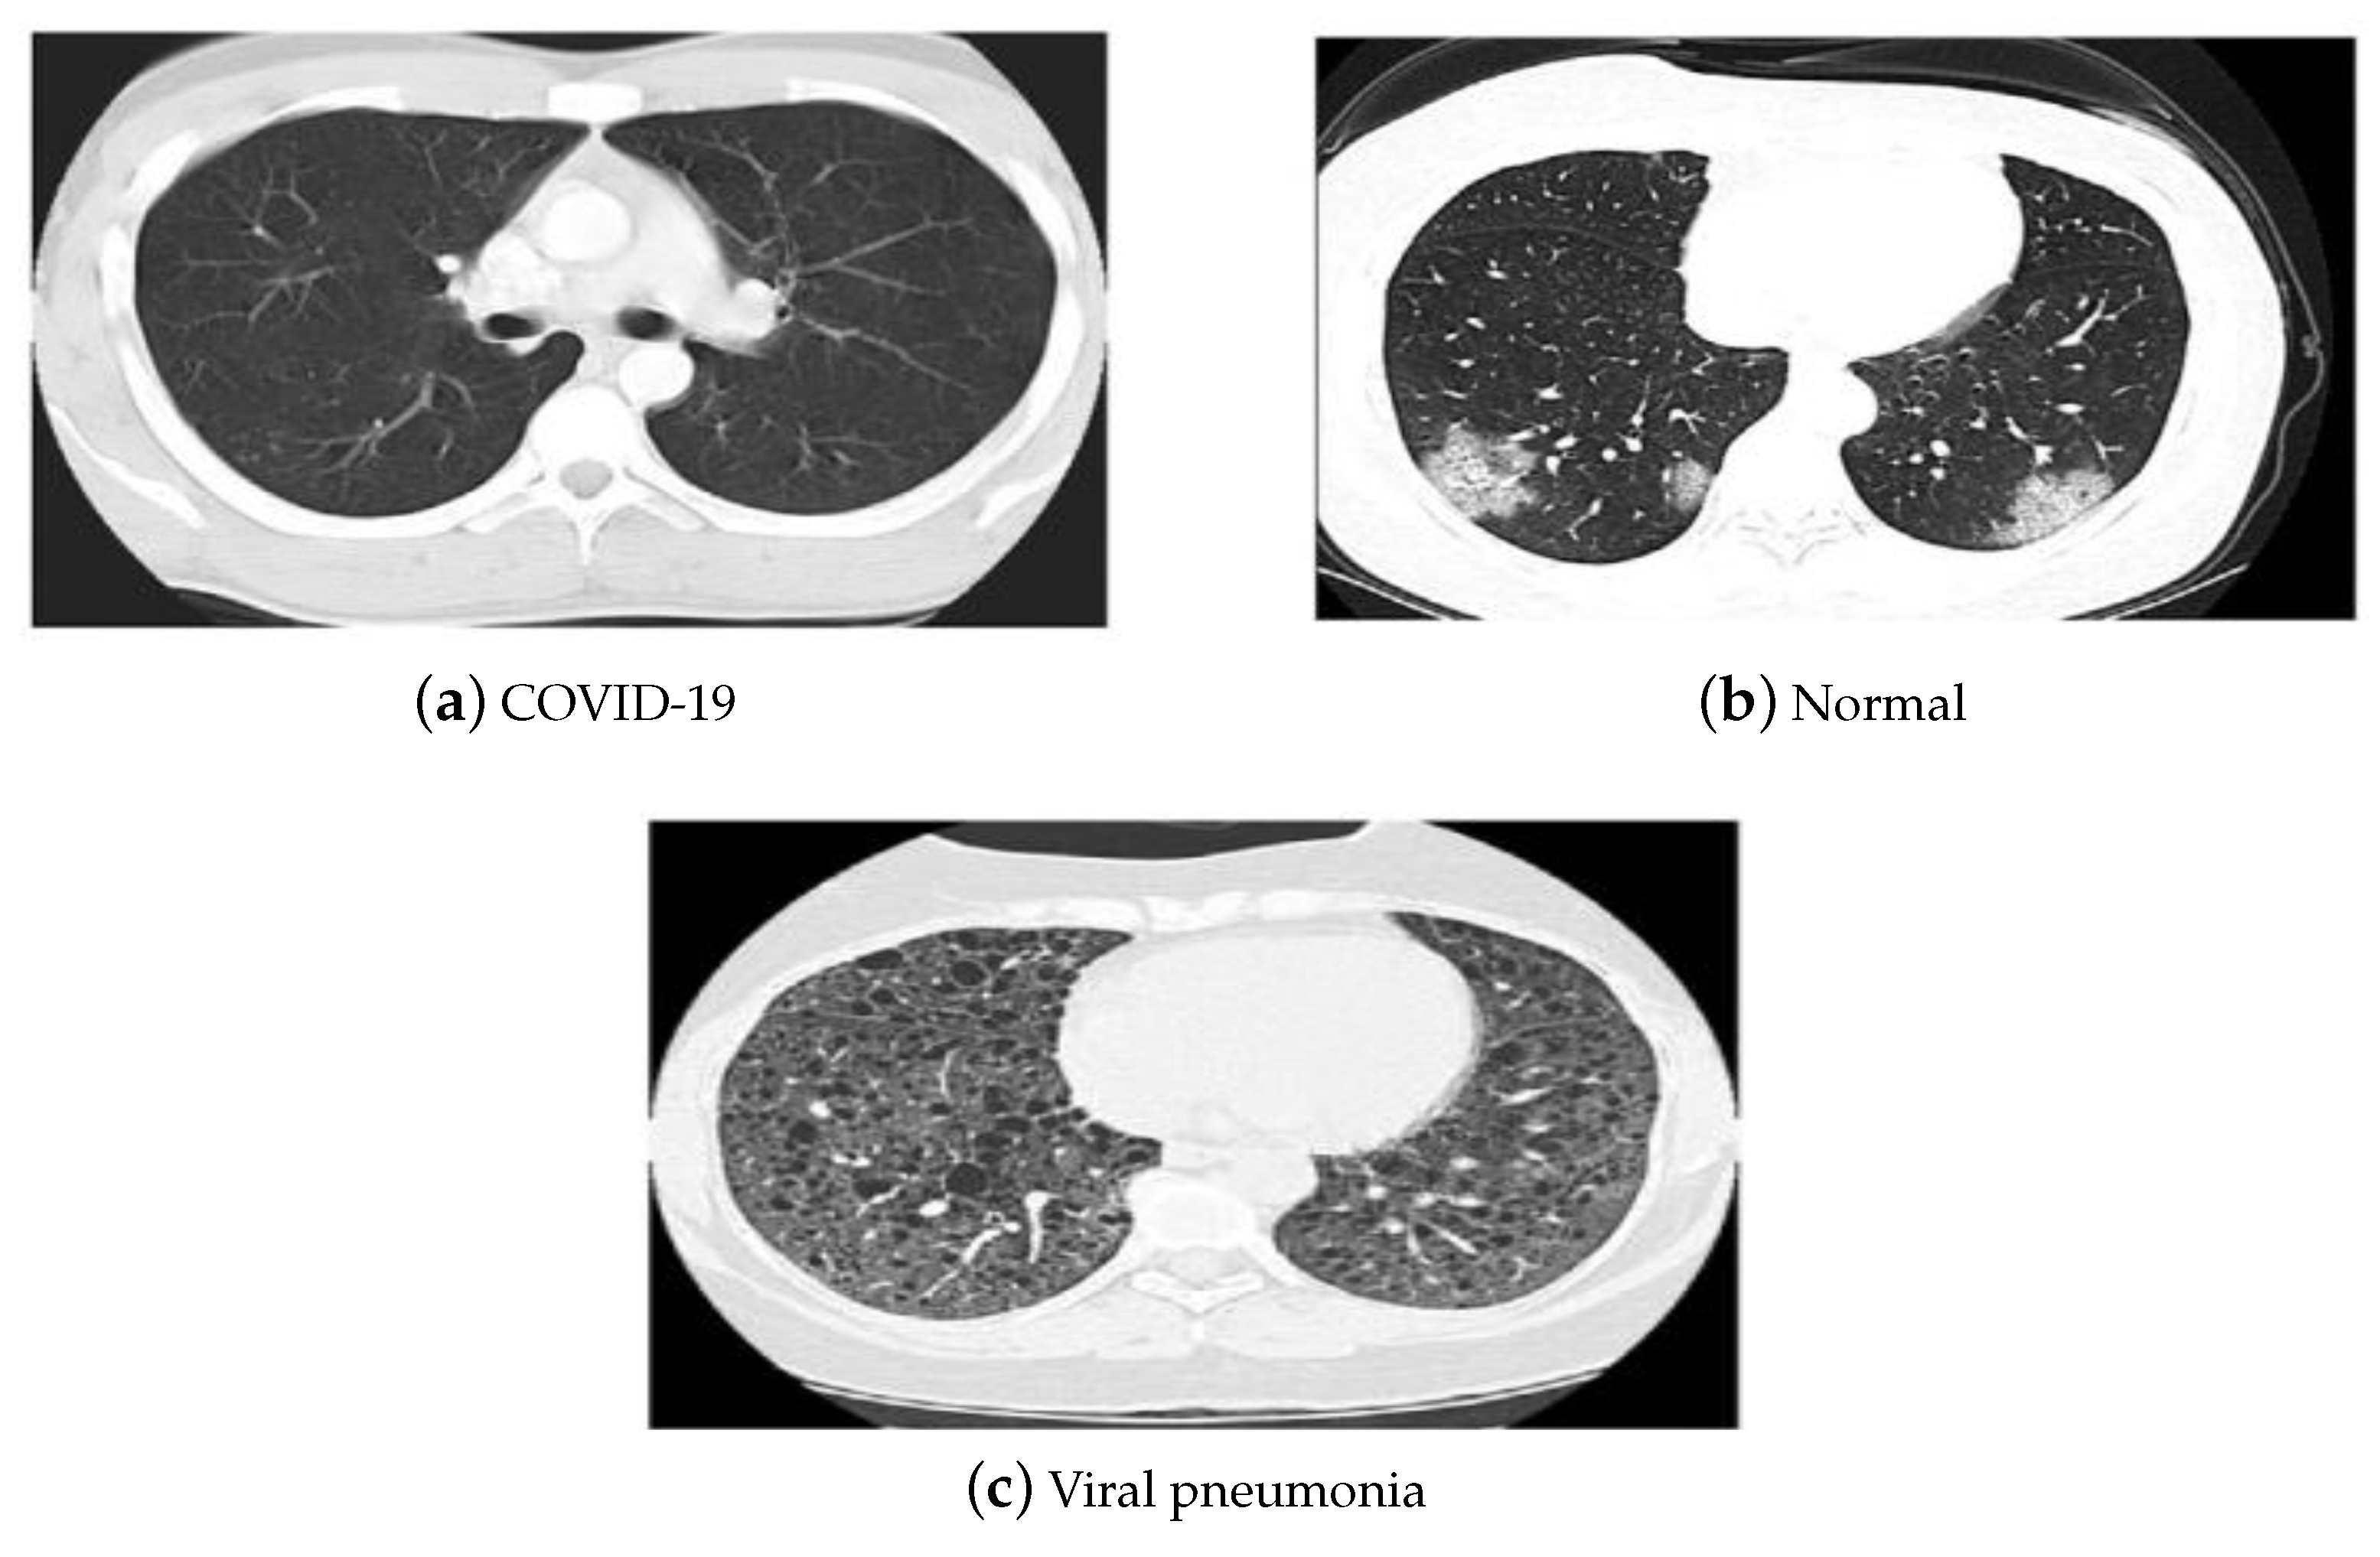

- Normalization: To improve the convergence of the training phase, input pixels to any AI system must have a normalized data distribution. To normalize an image, the distribution’s mean value is first subtracted from each pixel, then divided by the result by the standard deviation. Sample X-ray and CT images are shown in Figure 2 before (on the left) and after (on the right) the preprocessing steps.